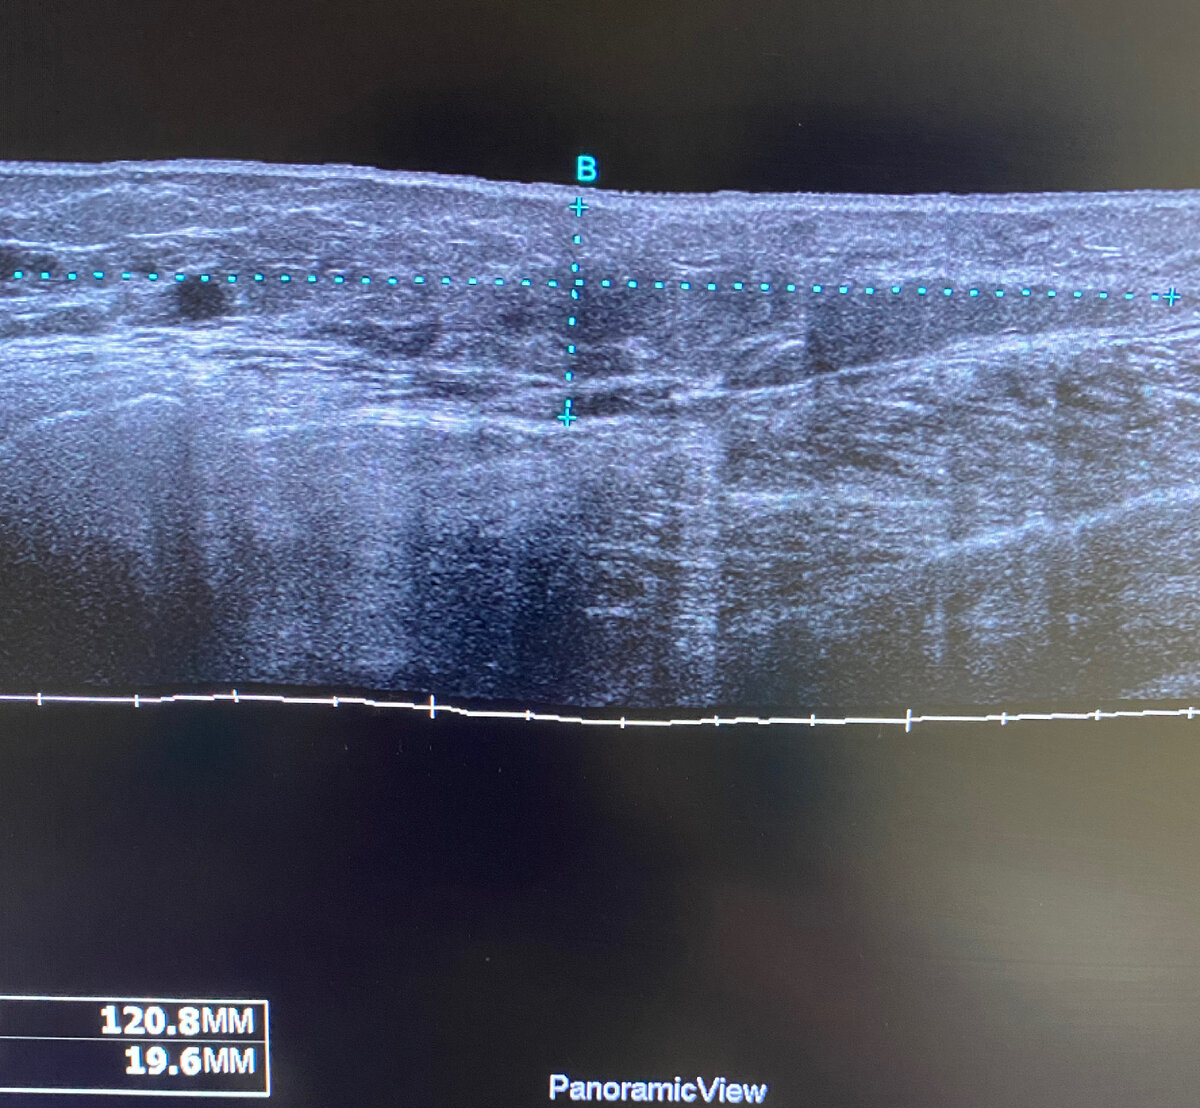

Представляю вам случай наличия безоболочечного геля  в мягких тканях бедер и голеней с обеих сторон. Посмотрите как по разному могут выглядеть скопления ПААГ в зависимости от места введения и реакции тканей. В данном случае гель локализуется внутримышечно, в подкожно-жировой клетчатке в виде гелеом, а также в ПЖК в виде диффузного распространение геля и фиброзных изменений ткани (нет четкой дифференцировки кожи и гиподермы). В одном случае есть гелеома с воспалением. Хорошую визуализацию распространённости геля для лечащего врача дают панорамные снимки.